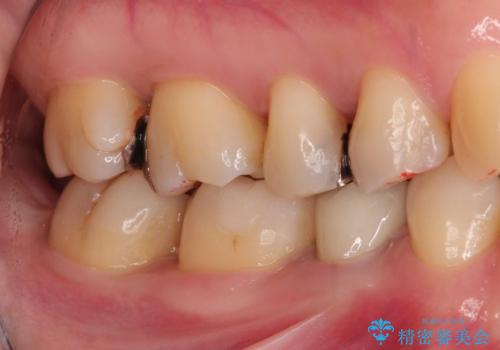

笑った時に見える金属を白くしたい

- 笑った時に見える金属を白くしたいとのことでメタルフリーの治療を希望され来院されました。

根管治療を行なったのち、オールセラミッククラウンにて修復処置を行っております。